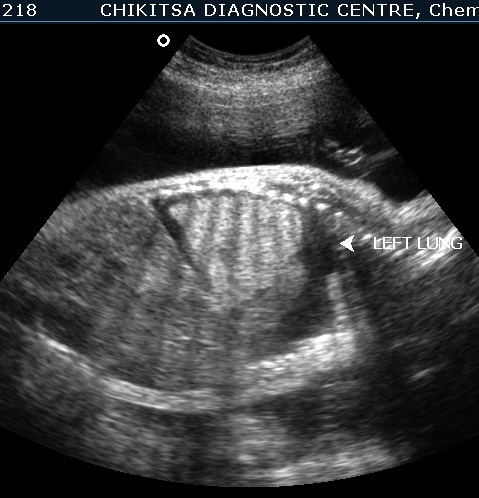

The left lung is hyperechoic and enlarged.

The heart is pushed to the right side, is compressed and therefore small.

The right lung is compressed and hypoplastic.